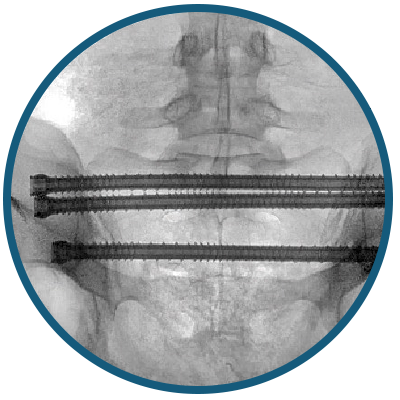

iFuse TORQ TNT™ Implant: the first 3D-printed, porous, threaded implant with lengths capable of spanning the posterior pelvis, passing through the ipsilateral ilium, sacrum, and through the contralateral ilium (through and through, "TNT").

- Pelvis-Specific 8.7 mm Diameter Fits 95% of S1 corridors suitable for a 7.3 mm transsacral screw2. 150% stronger in bending vs 7.3 mm stainless steel screw3, 4

- TORQLock™ Threads Hooked Profile Designed to reduce toggle

Designed to reduce loosening through pelvis-specific fixation. Variable thread heights and leads tailored to the posterior pelvis.